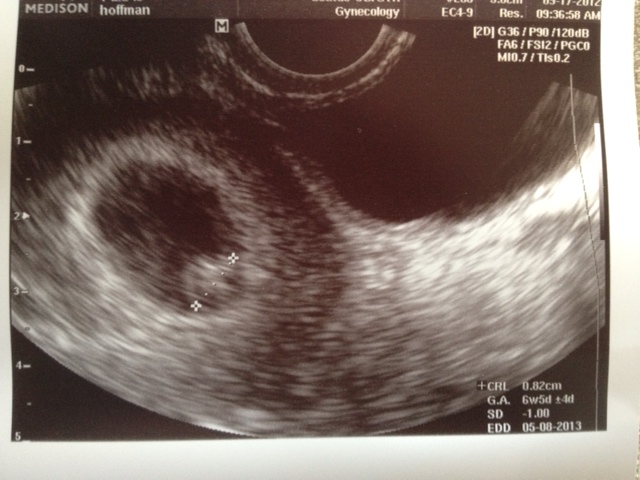

Well, we weren’t supposed to have our first ultrasound until the 28th. But a brief scare Sunday night led to an early look at our baby Monday morning. First things first, baby is fine! Measuring 3 days smaller than I thought it should (6 weeks 5 days, instead of 7 weeks 1 day), but the nurse practitioner said their equipment has a margin of error of +/-4 days, so she wasn’t worried. The best part was we got to see a heartbeat! We never got to see that last time. The nurse estimated it was probably beating around 140-160 beats per minute, which is right where it should be.

Meet Baby Hoffman:

I called the doctor as soon as they opened, and they agreed to see us at 9:50 that morning. I was so nervous sitting in the waiting room, and then again sitting in the exam room waiting for the nurse practitioner. It seemed to take forever. As soon as I saw the heartbeat flicker, I instantly started hyperventilating. I was relieved, shocked and just a whole bunch of other emotions all at once. The NP had to remind me to breathe, and said that everything looked exactly as it should. No idea where the bleeding had come from, but it had stopped by that point anyway. She told me that a little bit of bleeding wasn’t anything to be worried about, but that she also understood how scary pregnancy can be after a miscarriage, and that if at any time I didn’t feel comfortable with something I could always come in to be checked out. I have to say, I am really liking my new doctor’s office so far. So, I get to go back in on the 28th for my normally scheduled appointment. As scared as I was for the bleeding episode I’m glad we got a sneak peek at the baby, and that I only have to wait 10 more days to see our baby again.